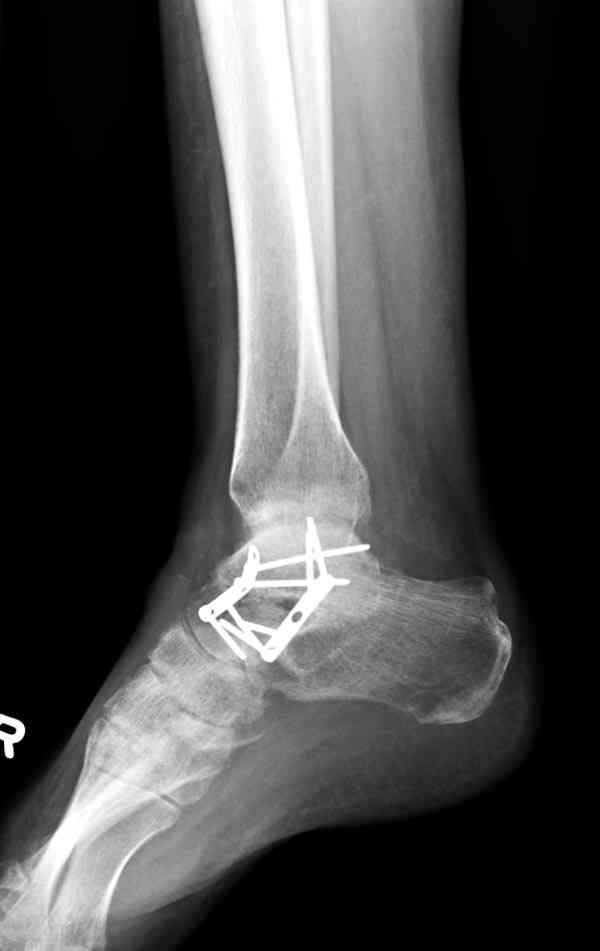

И второй случай из недавней ташкентской практики, (извините за качество ренгенограммы и только в одной проекции) случай падения с высоты (кстати моего друга - известного киноактера) - открытый

смещенный перелом тарана, с переломом переднего края дистального эпиметафиза большеберцовой кости.

При поступлении в приемной сделана первичная обработка с ушиванием открытой латеральной раны и вытяжением за пятку.

Из-за отсутствия времени пришлось оперировать на второе утро, из материала, что имеем на месте, фиксирован двумя шурупами, а третий-это контур сломанного жойстика в 4 мм. На дистальный медиальный конец тибиа antiglide 3.5 мм пластина. Через пару дней выписан и несмотря на предупреждение, самостоятельно начал нагрузку в 4 недели, время не ждет, снимается в боевике в Росийской Федерации.